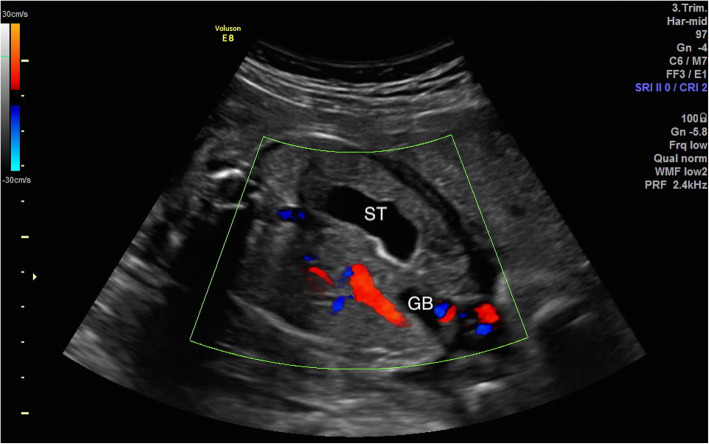

Fig. 2.

The gallbladder located between the umbilical vein and the stomach. GB, gallbladder; ST, stomach